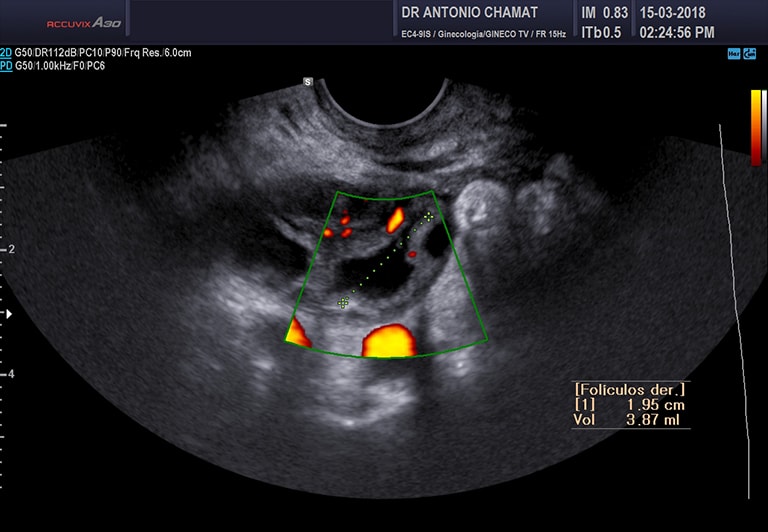

Foliculograma

Es un seguimiento ecográfico por vía transvaginal (3 ó 4 ecografías en total) con el objetivo de encontrar la fecha de ovulación y así determinar los días fértiles. Este estudio es útil en parejas con problemas de fertilidad y en mujeres con trastorno de la ovulación.